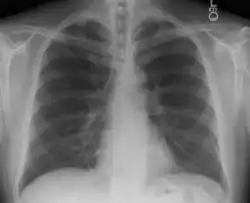

La radiographie médicale est la plus grande utilisation des rayonnements ionisants en médecine pour réaliser des images de l'intérieur du corps humain à l'aide de rayons X. Il s'agit de la plus grande source artificielle d'exposition aux rayonnements pour les humains. Toutefois, il ne s'agit pas d'une technologie nucléaire.